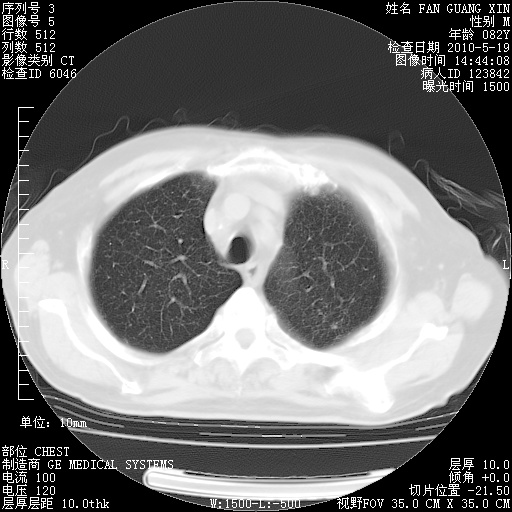

复查肺部CT,明显好转。为什么发热呢?

治疗3周后的肺部CT

治疗3周后的肺部CT纵隔窗